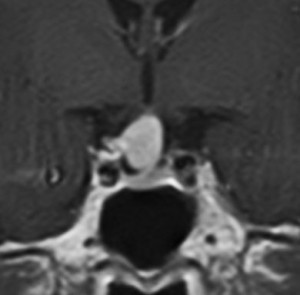

成人の下垂体柄に発生した小さな頭蓋咽頭腫です。のう胞性ですが石灰化もあり術前診断は可能でした。この頭蓋咽頭腫は,下垂体柄の内部から発生したものですから,下垂体柄が全周にわたってfunningしています。ちょうど前庭神経鞘腫における顔面神経のようなものです。また,冠状断で見ると下垂体柄が左に寄っているのが推測できますから,右側からアプローチします。腫瘍を観察しても,最初のうちは下垂体柄がどこにあるのかは解りません。